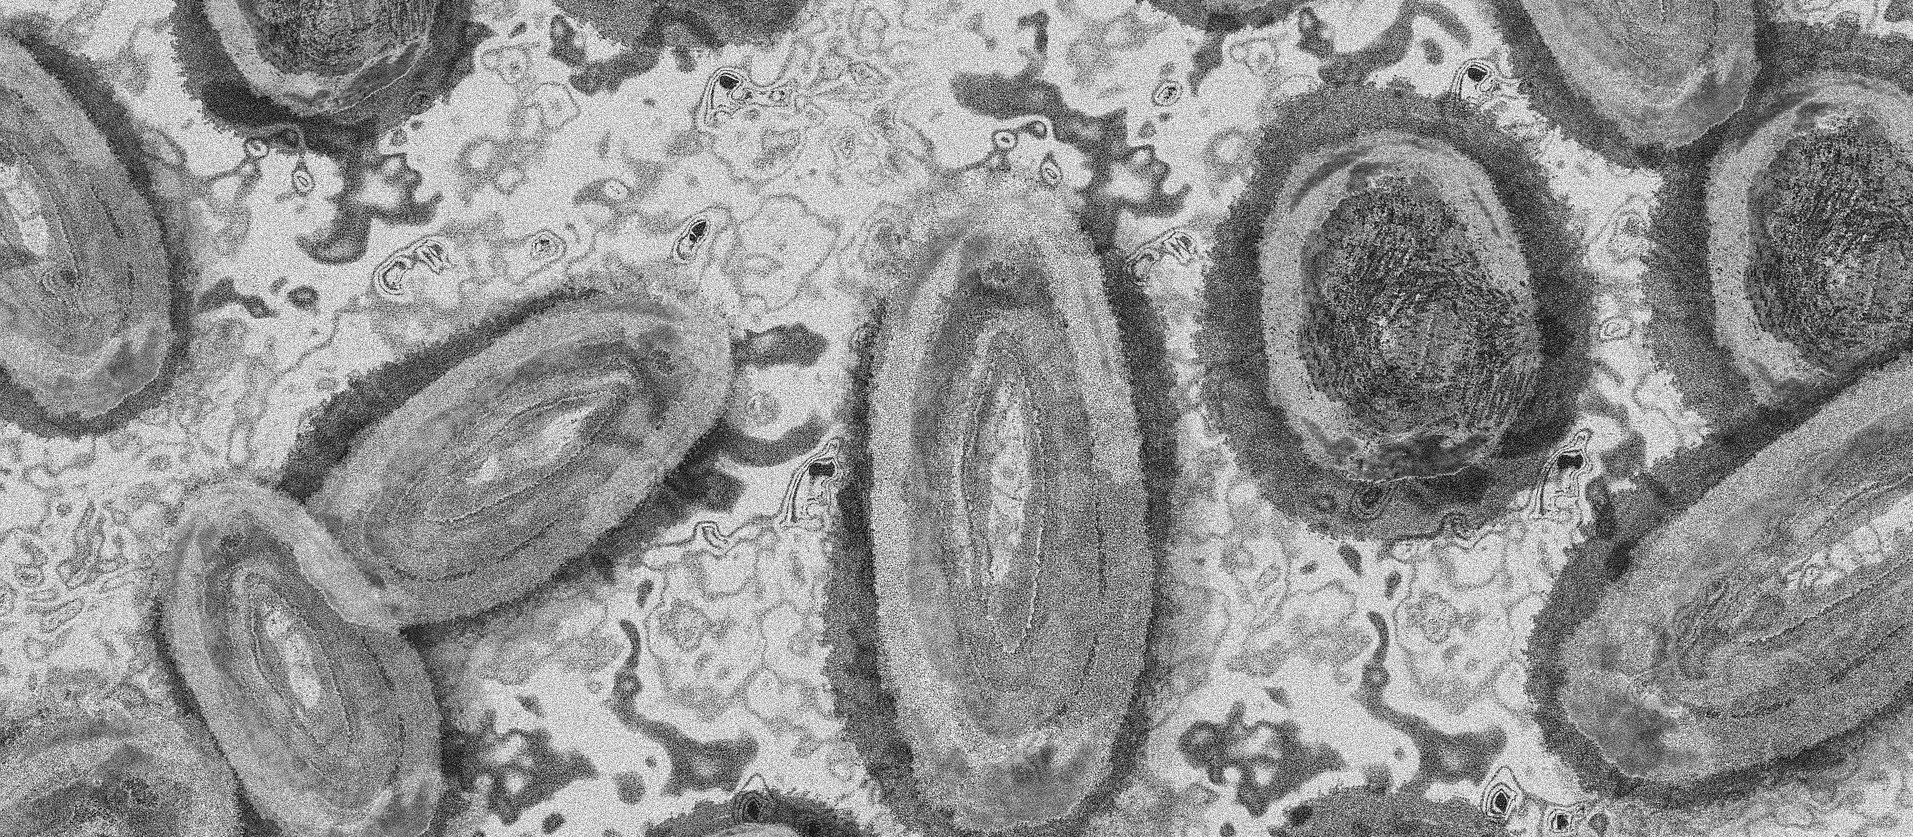

Imagem Ilustrativa/Representação abstrata do vírus da varíola/Gerd Altmann/Pixabay